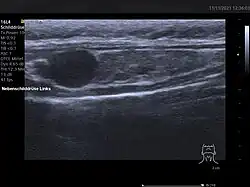

Vor einer geplanten Operation können Lokalisation und Größe der betroffenen Nebenschilddrüsenkörperchen durch Sonografie, Szintigrafie mit Technetium-99m-Sestamibi (Nebenschilddrüsenszintigrafie), Computertomographie oder Kernspintomografie dargestellt werden.

-

Nebenschilddrüse in der Sonographie -

Die Sensitivität dieser diagnostischen Verfahren ist jedoch begrenzt. Besonders bei komplizierteren Fällen, wie zum Beispiel bei Vorhandensein von mehreren auffälligen Nebenschilddrüsen oder entfernt auftretenden Nebenschilddrüsenadenomen, kann eine zuverlässige Lokalisation aller betroffenen Epithelkörperchen schwierig sein.[60] Neuere bildgebende Verfahren, wie Positronenemissionstomographie (PET) mit speziellen Radiopharmaka wie 68Ga-Trivehexin, können in solchen Fällen eine zuverlässigere Lokalisation ermöglichen,[61] wodurch deren komplette chirurgische Entfernung und damit eine vollständige Heilung des primären Hyperparathyreoidismus wahrscheinlicher wird.